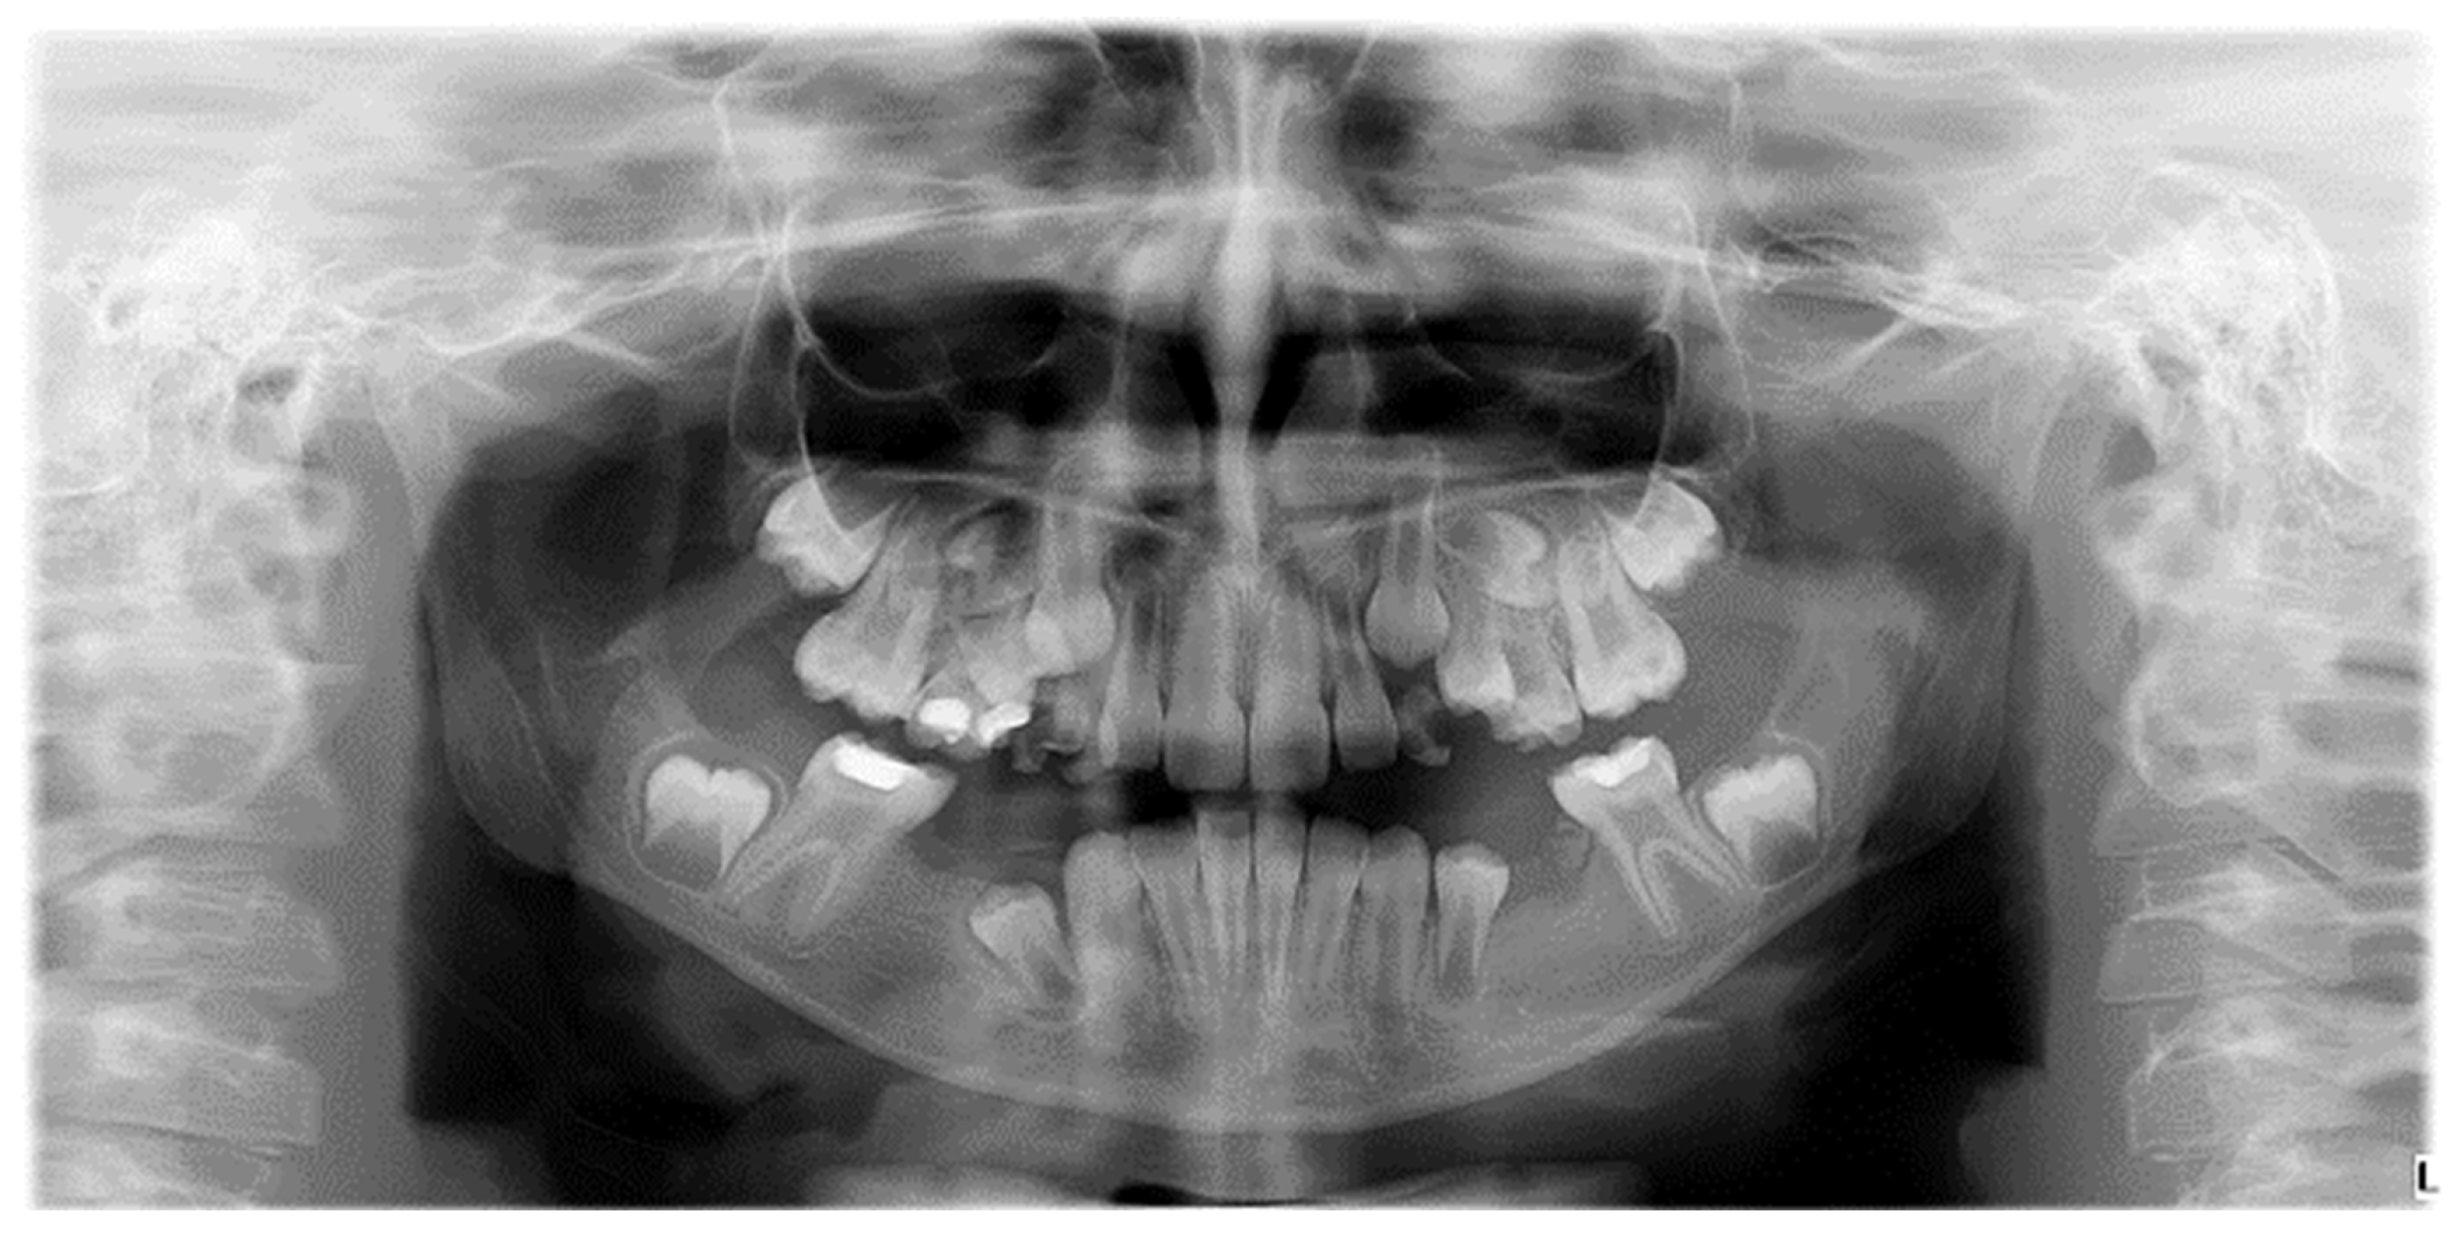

Numerical anomalies (agenesis, supernumerary teeth) did not account for the presence or absence of wisdom teeth. The diagnosis was made following clinical examination, anamnesis, and medical history, with dental extractions excluded. Numerical anomalies were confirmed radiographically, based on an orthopantomogram taken with Pax Flex 3D +, Vatech X-ray machine, VATECH Dental Manufacturing Ltd., Sutton, UK, with an exposure time of 12.9 s, 80 kVp, and 9.0 mA (Figure 5).

Figure 5.

Orthopantomogram of a patient with mixed dentition, clinical diagnosis of MIH, and radiographically certified hypodontia.